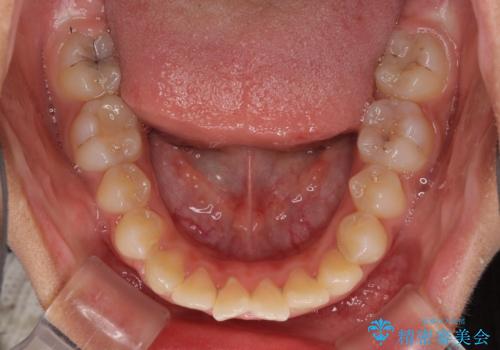

- 上下の出っ歯を気にして来院された患者様です。

口元を積極的に引っ込めるために、上下左右の第一小臼歯を4本抜歯することとしました。

前歯部の突出と開咬は、舌突出癖によるものでしたので、舌のトレーニングをしっかりと行っていただき、1年半程度と短期間で治療を終えることができました。